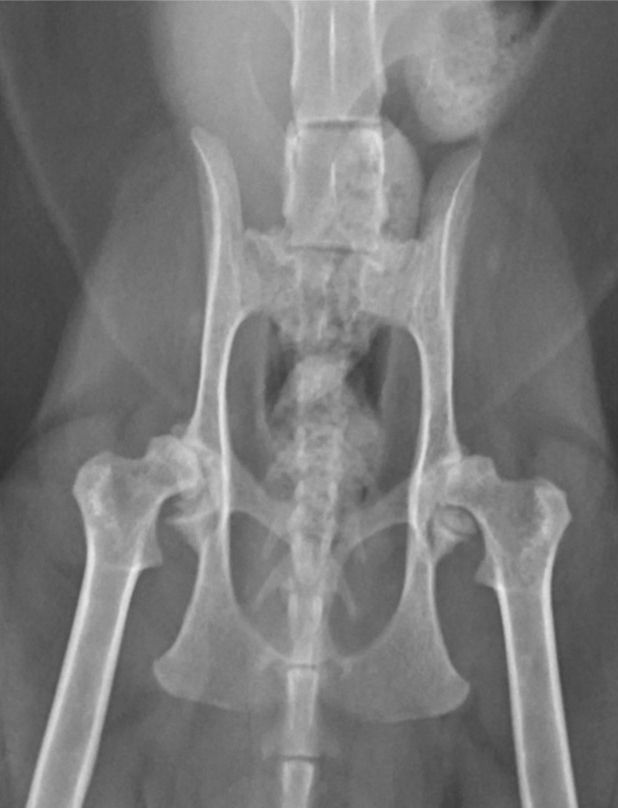

Radiografia

Apesar de suas limitações, a radiografia continua sendo o método mais utilizado para diagnosticar a osteosteoartritertrite em gatos, devido à sua ampla disponibilidade e percepção de custo-efetividade. No entanto, é amplamente reconhecido que a radiografia só é capaz de detectar osteoartrite em estágios avançados ou graves [16]. As características radiográficas observadas no diagnóstico da osteoartrite felina incluem a presença de osteófitos, aumento da opacidade do osso subcondral, mineralizações intra-articulares e de tecidos moles, espessamento dos tecidos moles e efusão sinovial (Figura 3). Quando alterações degenerativas são observadas nas radiografias, as mudanças degenerativas histológicas confirmam a presença de osteoartrite com alta especificidade [16].

No entanto, a radiografia é uma modalidade de imagem bidimensional, o que significa que alterações fora das estruturas esqueléticas ou próximas às bordas podem não ser facilmente visíveis [16]. Além disso, é impossível visualizar a cartilagem por meio de radiografias, e os achados radiográficos não estão bem correlacionados com a degeneração da cartilagem; um estudo constatou que até 71% das articulações femorais felinas com evidências macroscópicas de osteoartrite não apresentavam lesões associadas nas radiografias [17]. Essas limitações reduzem a eficácia da radiografia na detecção precoce ou leve da osteoartrite. De fato, um estudo recente observou que a radiografia não conseguiu detectar nenhuma articulação diagnosticada com osteoartrite leve histologicamente [16].

Apesar das limitações, a radiografia muitas vezes é a única modalidade de imagem disponível e, portanto, sua interpretação deve ser otimizada. Ter consciência de onde e do que procurar facilitará o diagnóstico precoce. O desenvolvimento de osteofitose pode ser mais lento em gatos do que em cães [2],[4], e outros sinais radiográficos, como diferentes tipos de formação óssea, podem ter uma relevância maior [17]. Embora os osteófitos sejam frequentemente considerados a principal característica radiográfica da osteoartrite, em felinos isso só parece ser verdade para a articulação coxofemoral [17],[18]. Para o cotovelo, tarso e joelho, as características radiográficas mais comuns são, na verdade, mineralizações associadas à articulação, proliferação óssea dorsal do tarso-metatarso e mineralizações intra-articulares, respectivamente [17]. Portanto, é essencial examinar minuciosamente as radiografias das articulações felinas em busca dessas outras formações ósseas ao redor das articulações e estar atento aos sinais de crescimento de osteófitos. Além disso, é fundamental lembrar das limitações da radiografia no diagnóstico precoce da osteoartrite. Quando há suspeita dessa condição, mas os sinais radiográficos não são evidentes, é importante buscar modalidades de diagnóstico mais sensíveis.

a

Figura 3. Imagens representativas demonstrando as alterações radiográficas comumente associadas à osteoartrite felina. Na visão ventrodorsal dos quadris (a), pode-se apreciar a formação de osteófitos nas margens acetabulares craniodorsais, além do remodelamento das cabeças femorais. Na visão mediolateral do cotovelo (b), pode-se apreciar um aumento da opacidade óssea subcondral na região peritrocilar, além da formação de osteófitos periarticulares. Na visão mediolateral do joelho (c), pode-se apreciar mineralização intra-articular e efusão sinovial. © Karen Perry